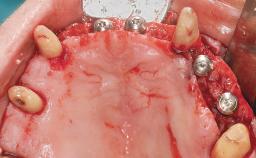

Immediate Loading of Eight Implants in the Maxilla and Six Implants in the Mandible and Final Restoration with Three-Unit and Four-Unit FDPs

Extensive scientific evidence has confirmed that immediately loaded implants with fixed full-arch provisional restorations can osseointegrate with success rates similar to conventionally or delayed loaded implants. A number of immediate-provisionalization techniques for edentulous jaws have been described. Some protocols differ when it comes to prefabricated provisional templates versus complete denture conversion; intrasurgical impressions versus direct relining; and cemented versus screw-retained provisional restorations. In this context, complete-denture conversion has been proposed for either intrasurgical impressions or direct relining. Another possibility is the utilization of a prefabricated provisional to be adapted either in the mouth (by direct relining) or in the laboratory (on a working model obtained from an intrasurgical impression).

Defining Characteristics Fully edentulous upper jaw to be rehabilitated with four or more implants

Modality 6+ implants with immediate loading

Loading Protocol Immediate